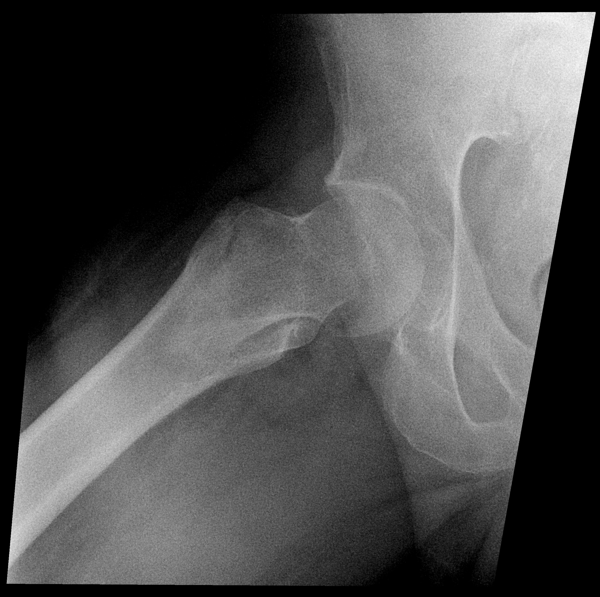

Решающее значение в установлении диагноза перелома шейки бедра имеет рентгенография тазобедренного сустава. У пожилых пациентов приведенные выше симптомы могут проявляться нечетко, а такие заболевания как инсульт или невропатия, вообще, не позволят поставить правильный диагноз без рентгена. Где сделать рентген? Перелом шейки бедра всегда сопровождается сильной болью, поэтому любые лишние движения оборачиваются новыми мучениями, а сопутствующие заболевания внутренних органов усугубляют ситуацию! Решение есть - воспользоваться уникальной услугой – цифровой рентген на дому. К вам приедет врач рентгенолог-травматолог, который выполнит весь комплекс лечебно-диагностических мероприятий и подробно расскажет, что делать дальше.

Получение качественных рентгеновских снимков на дому предъявляет серьёзные требования к рентгеновской аппаратуре. Далеко не каждый переносной рентгенаппарат позволяет получать снимки необходимого качества, чтобы достоверно поставить диагноз. Используемый нами рентгенаппарат АРА 110/160 в комплексе с компьютерным радиографом позволяет получать цифровые рентгеновские снимки высокого качества у пациентов различной комплекции и является уникальной услугой в Санкт-Петербурге, предоставляемой на дому.